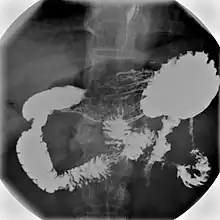

An upper gastrointestinal series, also called a barium swallow, barium study, or barium meal, is a series of radiographs used to examine the gastrointestinal tract for abnormalities. A contrast medium, usually a radiocontrast agent such as barium sulfate mixed with water, is ingested or instilled into the gastrointestinal tract, and X-rays are used to create radiographs of the regions of interest. The barium enhances the visibility of the relevant parts of the gastrointestinal tract by coating the inside wall of the tract and appearing white on the film. This in combination with other plain radiographs allows for the imaging of parts of the upper gastrointestinal tract such as the pharynx, larynx, esophagus, stomach, and small intestine such that the inside wall lining, size, shape, contour, and patency are visible to the examiner. With fluoroscopy, it is also possible to visualize the functional movement of examined organs such as swallowing, peristalsis, or sphincter closure. Depending on the organs to be examined, barium radiographs can be classified into "barium swallow", "barium meal", "barium follow-through", and "enteroclysis" ("small bowel enema"). To further enhance the quality of images, air or gas is sometimes introduced into the gastrointestinal tract in addition to barium, and this procedure is called double-contrast imaging. In this case the gas is referred to as the negative contrast medium. Traditionally the images produced with barium contrast are made with plain-film radiography, but computed tomography is also used in combination with barium contrast, in which case the procedure is called "CT enterography".[1]

Various types of barium X-ray examinations are used to examine different parts of the gastrointestinal tract. These include barium swallow, barium meal, barium follow-through, and barium enema.[2] The barium swallow, barium meal, and barium follow-through are together also called an upper gastrointestinal series (or study), whereas the barium enema is called a lower gastrointestinal series (or study).[3] In upper gastrointestinal series examinations, the barium sulfate is mixed with water and swallowed orally, whereas in the lower gastrointestinal series (barium enema), the barium contrast agent is administered as an enema through a small tube inserted into the rectum.[2]

X-ray images are then taken in a supine position at intervals of 20–30 minutes. Real-time fluoroscopy is used to assess bowel motility. The radiologist may press or palpate the abdomen during images to separate intestinal loops. The total time necessary for the test depends on the speed of bowel motility or transit time and may vary between 1 and 3 hours.[17]